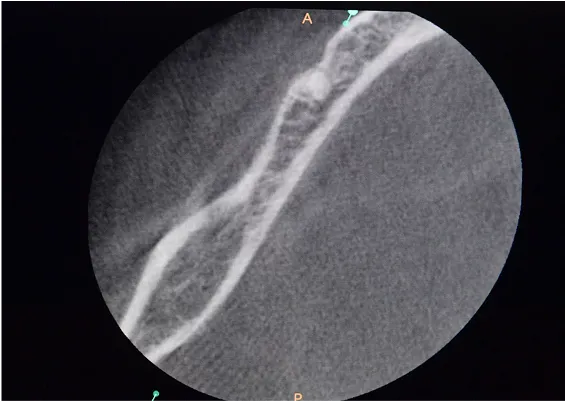

TRANSPOZYCJA NERWÓW ZĘBODOŁOWYCH DOLNYCH – IANT

Ta szczególna metoda używana jest w obszarze dolnego łuku zębowego w sytuacji braku dostatecznej ilości kości na wysokość. Metoda stosowana jest w sytuacji rozległych zaników kostnych w bocznych odcinkach żuchwy, w której wprowadzenie implantów groziłoby uszkodzeniem gałązek nerwowych nerwów zębodołowych dolnych. Gałązki nerwowe biegną wraz z naczyniami krwionoś-nymi we wspólnej pochewce w kanałach kostnych, umieszczonych symetrycznie po obu stronach w trzonach żuchwy.

Technika polega na chirurgicznym ich przemieszczeniu, a przez to stworzeniu bezpiecznego miejsca dla wszczepienia implantów o odpowiednej długości, co gwarantuje ich stabilną pozycję. Stosuje się ją wraz z zabiegiem rekonstrukcji kostnej przy użyciu biomateriałów w formie granulatu i membran.

Zabieg ten stosowany jest rzadko, jako alternatywa rozległych regeneracji kostnych. Wybierany bywa jako alternatywa operacyjna tylko w sytuacji, gdy konwencjonalne metody odbudowy kostnej są niewystarczające lub generują ryzyko braku skutecznej odbudowy kostnej celem wszczepienia implantu.